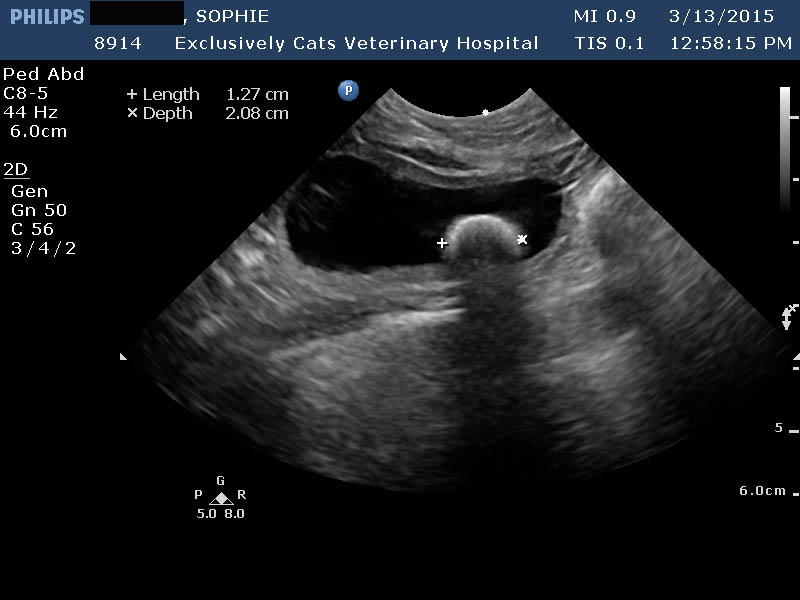

In

| Ultrasound image: One large stone in a cat bladder |

some cases, we identify bladder stones when taking an x-ray for an entirely

different reason. Some

stones are more likely to be seen on an x-ray than

others. Calcium oxalate stones are much more visible on x-ray than struvite

stones (about 80% of cases involving oxalate stones can be seen on x-ray).